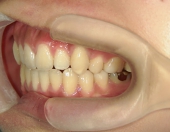

その後、伊藤歯科医院に入社し、やっと矯正をする機会に恵まれました。矯正しているのが目立ちにくい治療を希望し、舌側ワイヤー矯正に挑戦することになりました。

はじめて歯の裏側に器具をつけた時は違和感がとてもあり、特に「さ行」が発音しづらかったのを覚えています。舌が器具に当たりやすいので、傷付きやすく、スペースが狭いため窮屈な感じがしました。

はじめは気になることばかりでしたが、2,3週間するとすっかりと慣れ、しゃべりづらさも改善してきました。それと同時に歯並びも動き始め、月に一回調整をする度に自分で歯の写真を撮って変化を楽しみました。舌側矯正だったので、あまり周囲の人から矯正をしていることを気づかれずに治せたことは嬉しかったです。ずっと悩んでいましたが、矯正をはじめるとあっという間に時間が過ぎていきました。